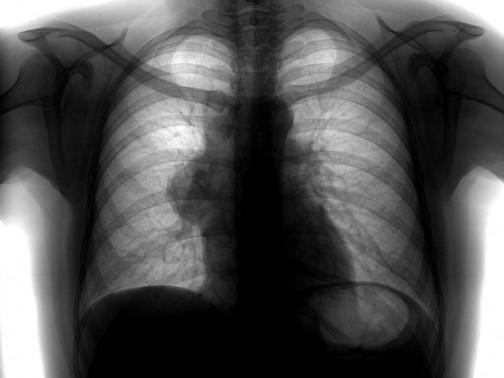

• Рентгенография:

о Крупное объемное образование с дольчатым контуром в переднем средостении

(а) Мужчина средних лет с жалобами на боли в груди. При рентгенографии органов грудной клетки в ПП проекции в левой половине переднего средостения определяется объемное образование с дольчатым контуром. На фоне образования визуализируется дуга аорты.

2. Рентгенография семиномы средостения:

• Крупное объемное образование с дольчатым контуром в переднем средостении